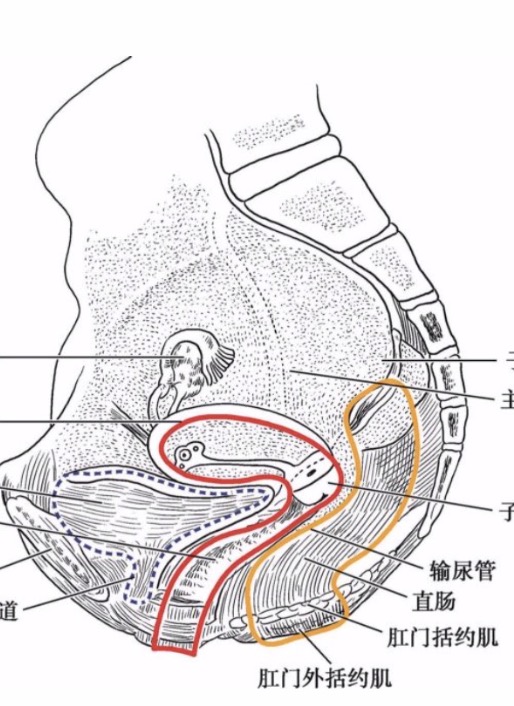

- 发挥支撑作用的结缔组织包括盆腔内筋膜、盆腔韧带及会阴隔膜。盆腔内筋膜是腹横筋膜延续至覆盖骨盆底,位于盆底肌之上,腹膜之上,包绕盆腔脏器并将其连接至支持的肌肉组织和骨盆的骨组织。这一结缔组织网与盆腔脏器表面的结缔组织纤维相交织,使盆腔脏器固定在正常解剖位置。盆腔内筋膜的特殊部位增厚形成了盆腔韧带,参与.....

- 妇产康复---盆地结缔组织-韧带 布骨产后恢复中心 ,2020-04-19

- 盆筋膜脏层连续性强,像网状结构分布在整个盆腔,在某些部位局部增厚,附着于邻近的骨面形成韧带,它们起着支撑和固定脏器位置的作用,如耻骨膀胱韧带、子宫骶韧带等。有些韧带内有少许平滑肌纤维,如子宫圆韧带、子宫主韧带、子宫骶韧带等;有些韧带中有进出脏器的血管、神经穿行(又称血管神经鞘),如膀胱侧韧带、直肠侧.....

- 妇产康复---盆腔结缔组织-筋膜 布骨产后恢复中心 ,2020-04-19

- 骨盆筋膜为腹内筋膜向下直接延续的一部分,位于盆部腹膜与盆膈之间。覆衬盆壁的内面及盆底,并延续包被盆腔脏器、血管和神经,形成它们的鞘、囊和韧带,对盆内脏器具有保护和支持的作用。盆筋膜分为盆壁筋膜、盆膈筋膜和盆脏筋膜。在盆腔内相邻两脏器之间、盆内脏与盆壁之间盆脏筋膜形成4个筋膜隔,分别位于膀胱的前面、膀.....

- 盆底解剖结构,女性盆底是由封闭骨盆出口的多层肌肉和筋膜构成,有尿道、阴道和直肠贯穿其中。盆底肌肉群、筋膜、韧带及其神经构成了复杂的盆底支持系统,其互相作用和支持,承托并保持子宫、膀胱和直肠等脏器在盆腔的正常位置。若盆底结构和功能发生异常,可影响盆腔脏器位置及功能,甚至引起分娩障碍,而分娩处理不当,亦.....